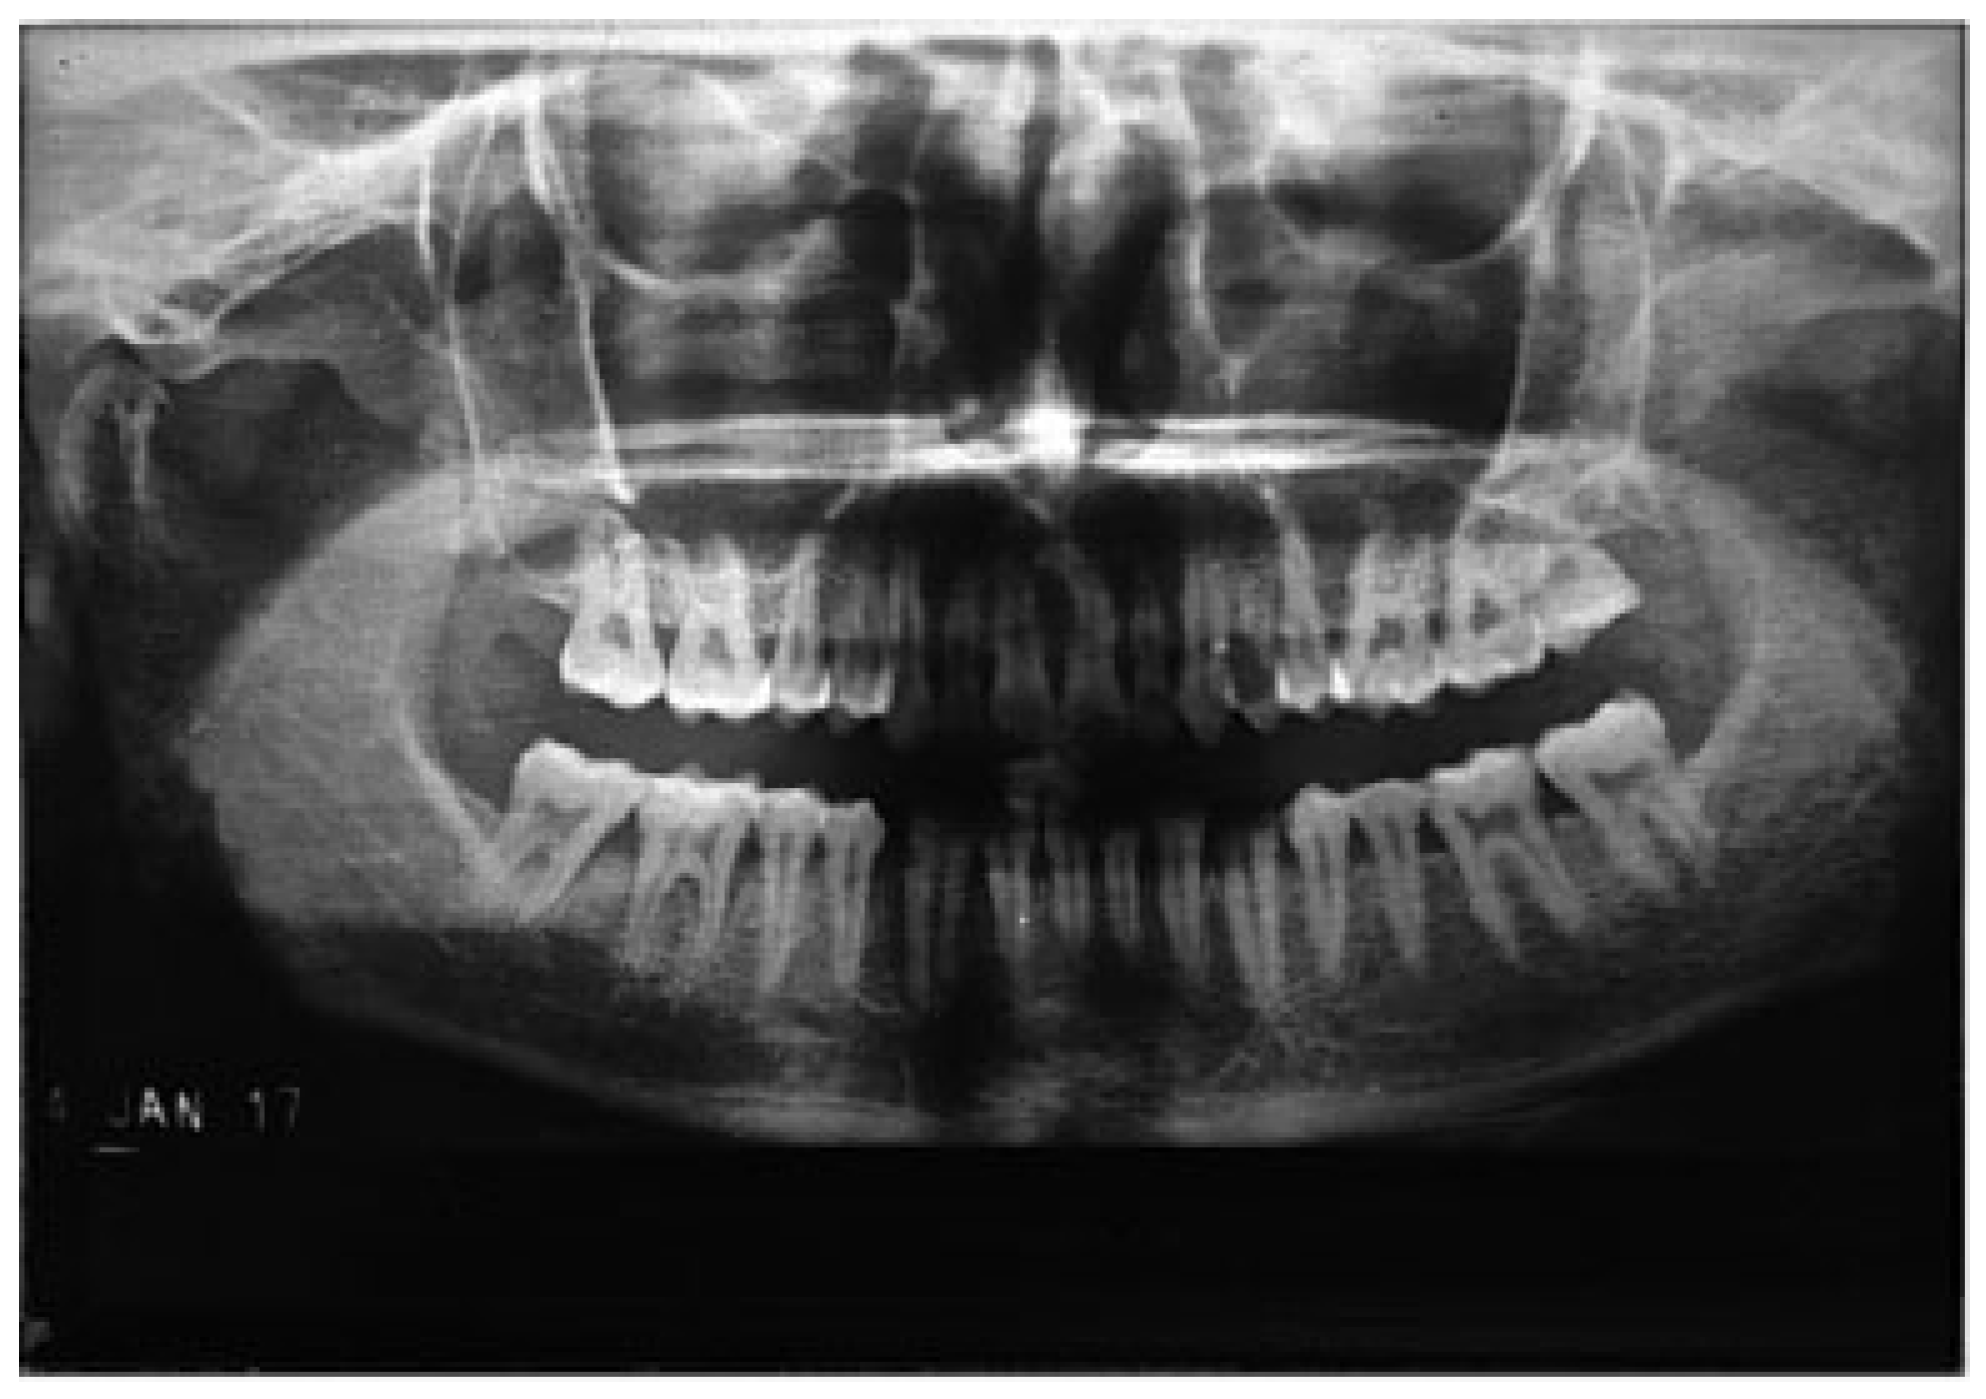

Figure 6. Right condyle fracture with the absence of mandibular third molar.

Of the mandibular angle fractures, 146 patients (97.33%) had mandibular third molars and 4 patients (2.67%) did not have third molars. The presence of a mandibular third molar in angle fractures was statistically and significantly higher than in patients who did not have them.

Of the condyle fractures, 76 patients (58.46%) had absence of mandibular third molars, whereas 54 patients (41.54%) had third molars. The absence of a mandibular third molar in condylar fractures was statistically and significantly higher than in patients where third molars were present (Figure 5, Figure 6, Figure 7 and Figure 8; Table 4).